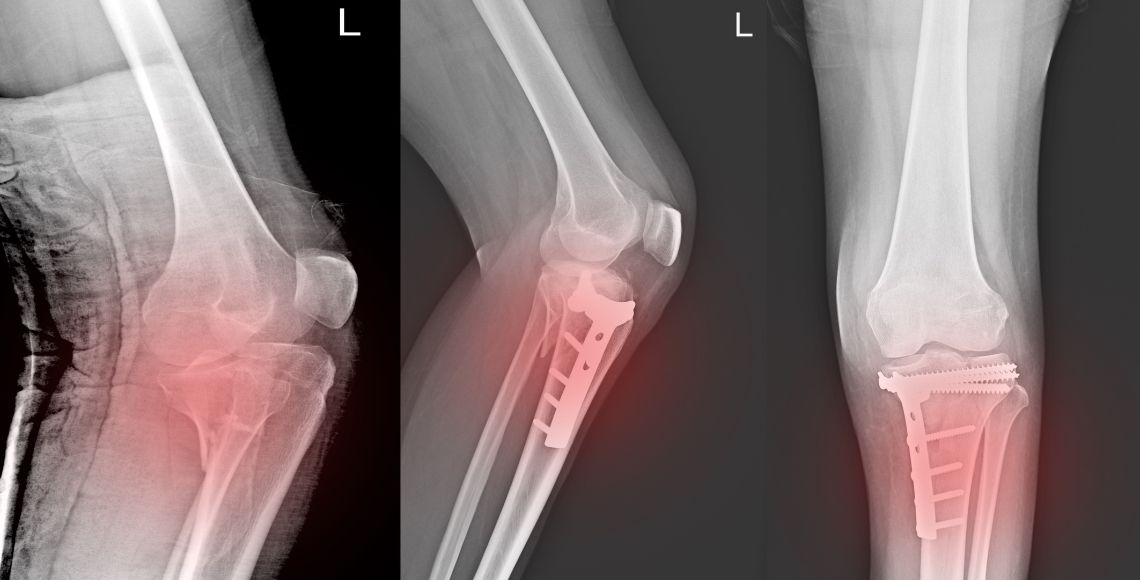

Ortopedija se bavi povredama i bolestima mišićno-skeletnog sistema. U Eurodijagnostici, specijalistički pregled vrši dr Stanislav Rajković iz Instituta za ortopediju Banjica.

Rendgen je efikasan dijagnostički alat za ispitivanje kostiju i pluća. U klinici Eurodijagnostika u Beogradu pregledi su brzi, bezbolni, sa minimalnim zračenjem i uz poštovanje Covid-19 mera.

Pregled ortopeda | 6.500 RSD |